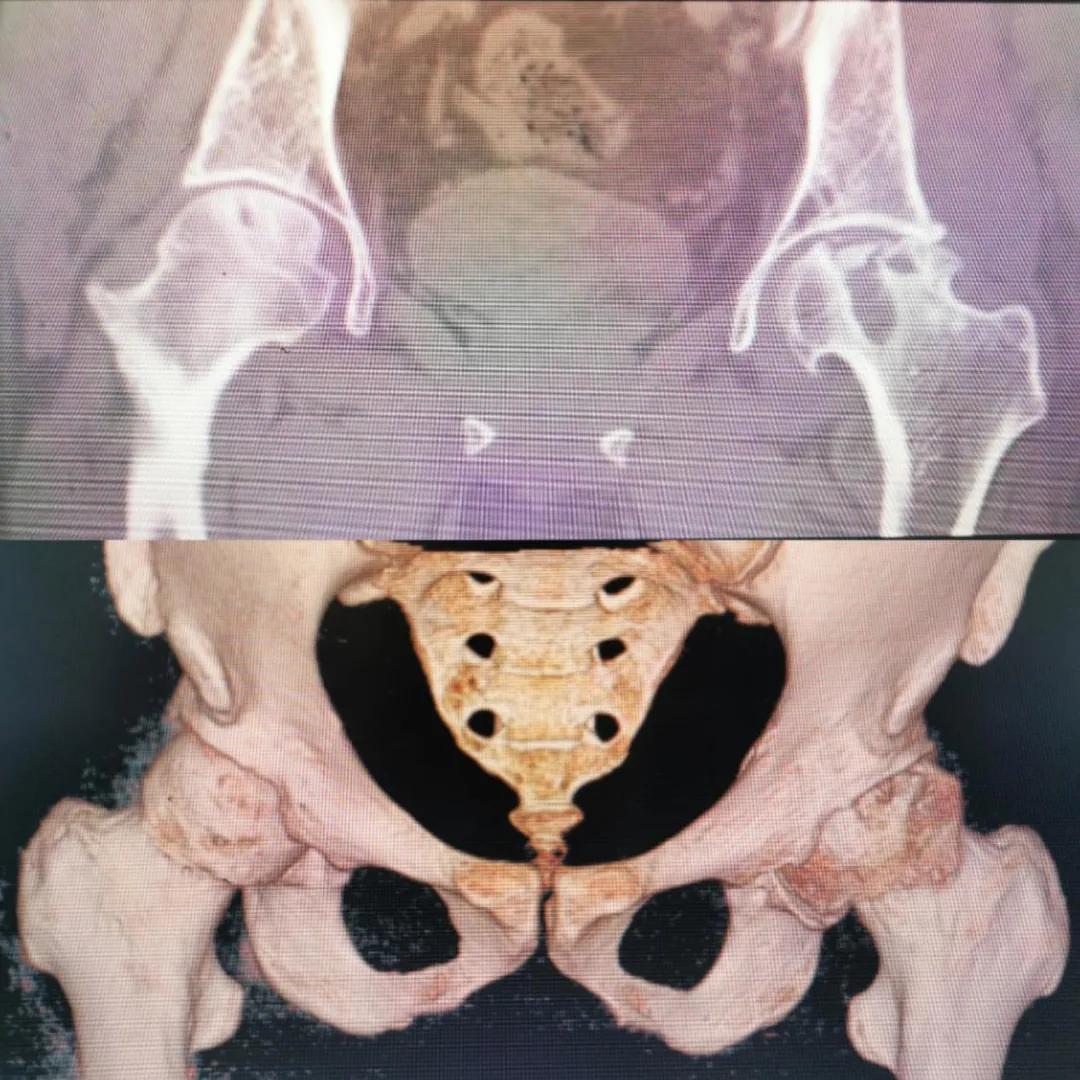

圖片(圖為患者入院時髖部CT檢查)

入院急查血結(jié)果提示炎癥反應(yīng),感染較重,凝血功能及肝功均不同程度損害;髖關(guān)節(jié)磁共振(MRI)檢查提示雙側(cè)股骨頭缺血壞死,繼發(fā)髖關(guān)節(jié)炎,左側(cè)髖周軟組織腫脹。醫(yī)療團隊給出的初步診斷為膿毒血癥、股骨頭缺血性壞死、軟組織感染、皮膚潰瘍及閉孔神經(jīng)損傷。

追溯病史,患者訴前不久曾用蜂蜇療法治療股骨頭壞死,每日4次,每次100只蜜蜂蜇雙臀部、髖部,這才導(dǎo)致了病情急劇進展。查明了來龍去脈,我院智能微創(chuàng)骨科醫(yī)護團隊與患者家屬積極溝通病情,給予特殊級抗生素抗感染以及消腫、止痛等支持治療,同時對潰瘍創(chuàng)面進行專業(yè)、規(guī)范的清創(chuàng)、換藥處理,保護創(chuàng)面降低感染程度;護理上輔助翻身,減少壓力性損傷。